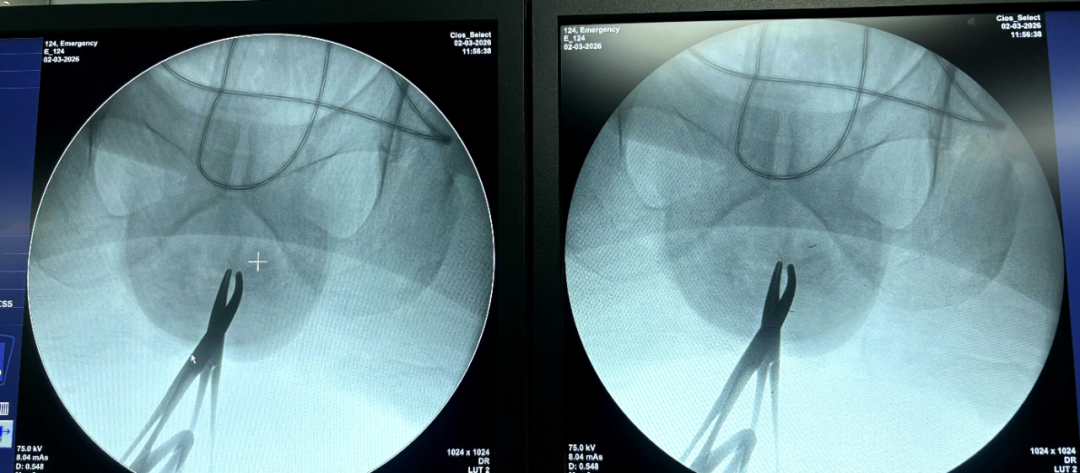

考虑到吻合钉深埋组织、常规肉眼难以定位,方松山主任团队制定微创取钉方案,术中借助 C 臂机实时透视定位,反复确认每一枚吻合钉的位置、深度,避免盲目操作损伤正常组织。

手术过程精准高效,团队在高清视野下精细操作,完整取出 7 枚残留吻合钉,全程创伤小、出血少,最大程度保护肛周功能。